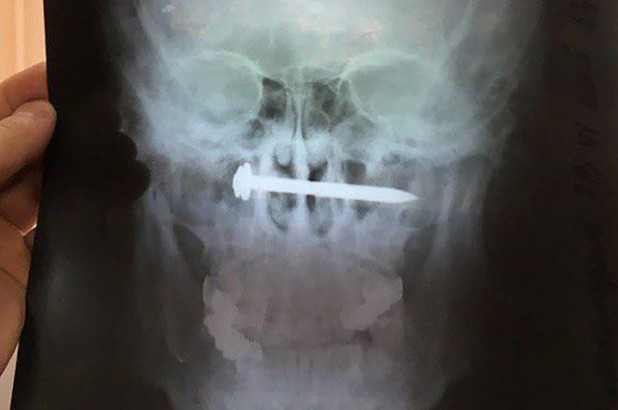

اكتشف الأطباء في روسيا وجود مسمار داخل رأس مريض كان يعاني من آلام شديدة مع صعوبات في السمع.

وبدأ الرجل، من مدينة إلبان الواقعة في إقليم "خاباروفسك كراي" الروسي، يعاني من فقدان القدرة على السمع، فراجع الطبيب لمعرفة سبب المشكلة، وكانت الصدمة عند اكتشاف مسمار مُثبت في دماغه ولم يستطع تذكر أي شيء عنه.

وأجرى الجراحون جراحة طارئة لإزالة المسمار من جمجمة المريض، ولحسن الحظ فقد كان على بعد سنتيمترات قليلة من الشرايين الرئيسية التي تزود دماغه بالدم.

ويعتقد الرجل وهو في الثلاثينات من العمر، أن المسمار اخترق رأسه، خلال قيامه بمشروع لترميم منزل وهو تحت تأثير الكحول، ومع ذلك، يقول المريض إنه لم يشعر بألم أثناء ذلك، وقام بفرك بعض المراهم العشبية على مكان الإصابة، دون أن يدرك أن المسمار كان لا يزال داخل رأسه.